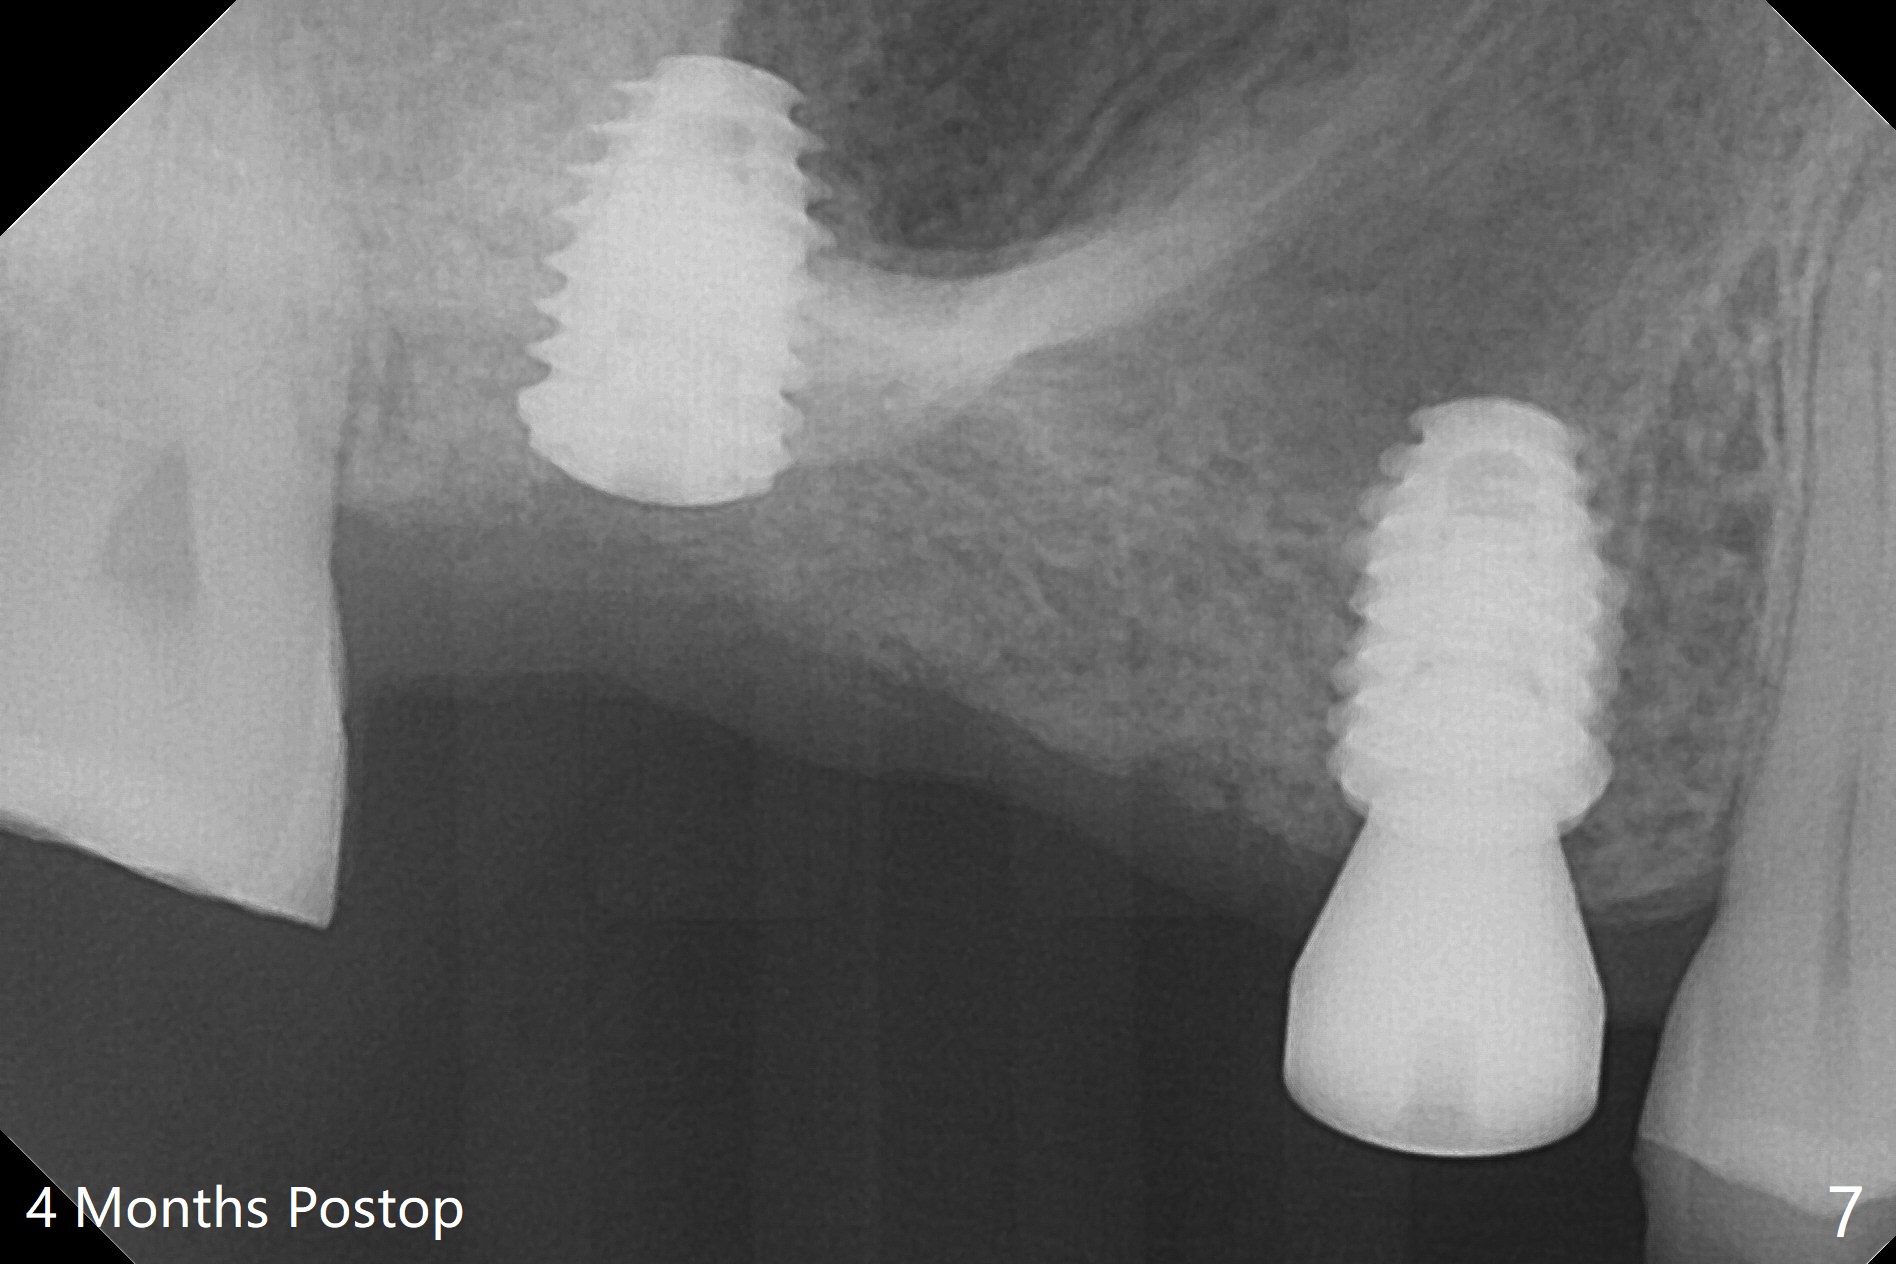

Eight months post socket preservation, the bone density at #2 feels low during osteotomy.  The site is underprep not only in depth, but also in diameter (4.0x7.3 mm with 10.5 mm offset), but a 5x7.3 mm implant is ~ 1 mm shy of the purposed depth.  Following 4.5x7.3 and 4.0x8.5 mm drills (without air leak), the implant reaches the depth, but with ~ 5 Ncm insertion torque (Fig.1).  Placement of the same sized implant at #4 (healed site) is smooth with satisfactory stability (~30 Ncm, Fig.2,3).  Ideally the site of #2 should have been prepared with sinus lift so that the apex of a longer implant would be engaged to the sinus floor for stability.  These two implants heal normally clinically and radiographically 1.5 months postop (Fig.4-6).  Bone surrounds the implant at #2 when it is uncovered 4 months postop (Fig.7).  The retainer at #4 looks short with large gingival embrasure (Fig.8 *) 6.5 months postop.  Finally the patient is ok with it because she does not like gingivectomy.  Provisional should have fabricated (Fig.9 light yellow curved lines) to create gingival scallops with secondary formation of papillae (arrows).